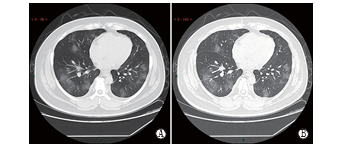

(1)双肺多发、斑片状、亚段或节段性磨玻璃密度影,被细网格状或小蜂窝样小叶间隔增厚分隔成“铺路石样”改变,CT扫描层厚越薄,磨玻璃密度影与小叶间隔增厚显示越清晰;高分辨率CT(high-resolution computed tomography,HRCT)呈现细网格状或小蜂窝样小叶间隔增厚内稍高密度磨玻璃密度改变、边缘模糊(图1,45例,54.2%,共计83例)。X线分辨较CT差,基本上表现为边缘模糊的磨玻璃密度影(图2,9例,10.8%,共计83例)。

图1 典型CT/X线影像表现(例1)

男性,38岁,无明显诱因发热(39.3℃)、干咳和气短3 d。实 验室检查,WBC:6.35×109/L(正常),LYMPH%:4.1(减低), LYMPH:0.31×109/L(减低),EO:0(减低),CRP:170.91 mg/L(升高),PCT:0.45 ng/ml(升高)。A(SL:6 mm)和B(HRCT)示双肺 多发斑片状+小叶网格状小叶间隔增厚,呈典型“铺路石”征象。